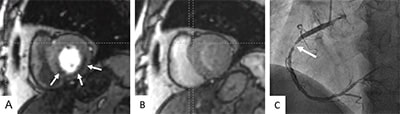

Bei der sogenannten „Stress MRT“ wird die Durchblutung des Herzmuskels unter pharmakologischer Belastung mittels Adenosin betrachtet. Durchblutungsstörungen können Hinweis auf relevante Einengungen der Herzkranzgefäße geben (Bild 2).

In der dynamischen Kontrastmitteldarstellung zeigt sich ein Kontrastierungsunterschied (Perfusionsdefizit) zwischen Adenosin-Stressbelastung (Pfeil in A) gegenüber der Ruheuntersuchung (B) in der Hinterwand der linken Kammer als Hinweis auf das Vorliegen einer Stenose bedingten Minderversorgung (Ischämie). Der invasive Herzkatheter bestätigte die relevante Stenose der rechten Herzkranzarterie (Pfeil in C).